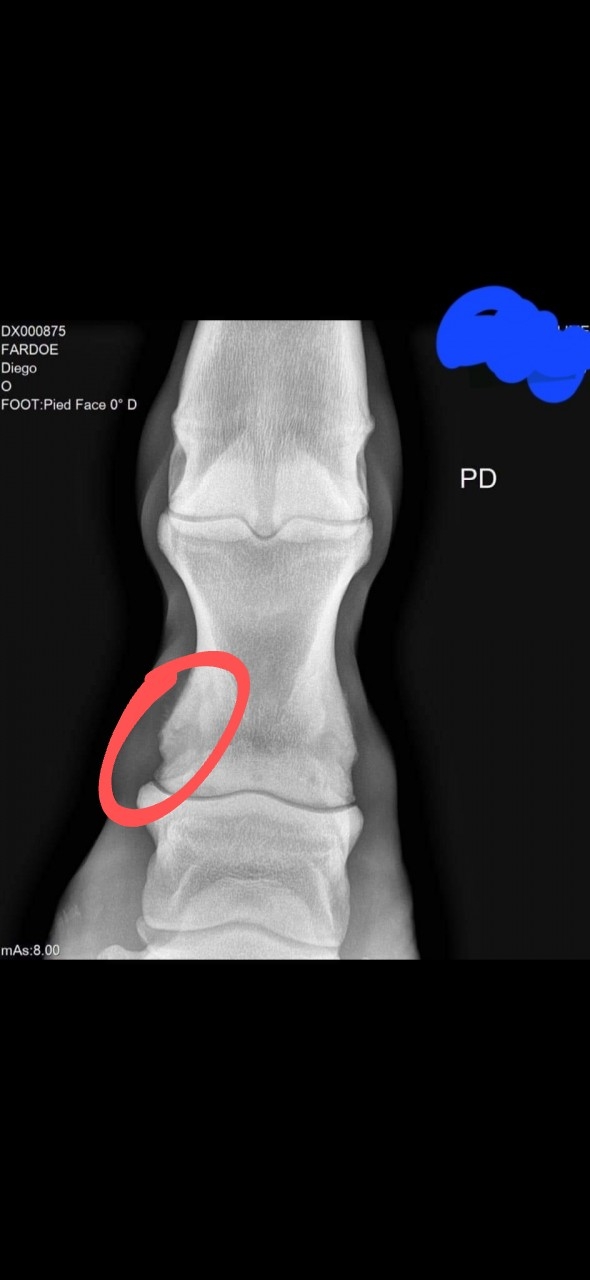

| Dire merci | ![]() Avec ce genre de radio, et légère déformation du paturon est ce que quelqu'un aurait une une idée des risques? Le cheval ne boite pas. C'est pour ma culture personnelle |

| Dire merci | ![]() C'est ça le défaut ? Alors je suis une bille la dedans, donc c'est une vraie question C'est dit quoi dans l'annonce ? |

| Dire merci | Je vois le même défaut que Choupifresh, et peut-être aussi sur l'autre coté et en diagonale en partant du défaut entouré. Ca a pas l'air d'être grand chose, peut-être une petite atteinte osseuse en faisant l'idiot poulain. Une très très légère arthrose traumatique ? A priori c'est "rien" et ça sera peut-être jamais rien, mais il peut aussi développer de l'arthrose dans le temps je pense que c'est pour ça qu'il est à venir chercher rapidement. Par contre vu le cheval ça m'étonnerait quand même qu'il parte pour pour 2000e... certainement pour 5-6k malgré tout, si ce n'est plus, et là ça fait cher le "risque". |

| Dire merci | Ahahaha je l'ai vu aussi ce cheval Mais tout comme toi je ne sais pas ce qui cloche sur la radio ![]() Après de toute façon c'est un peu toujours au petit bonheur la chance un cheval... Je connais des chevaux avec des radios dégueux qui n'ont jamais boité et vice versa. Mais je comprends qu'on préfère partir sur des radios impeccables (si ça existe) |

| Dire merci | Le mieux serait de demander un 2nd avis véto (et un vrai bon véto équin), en fonction de ce à quoi est destiné le cheval. |